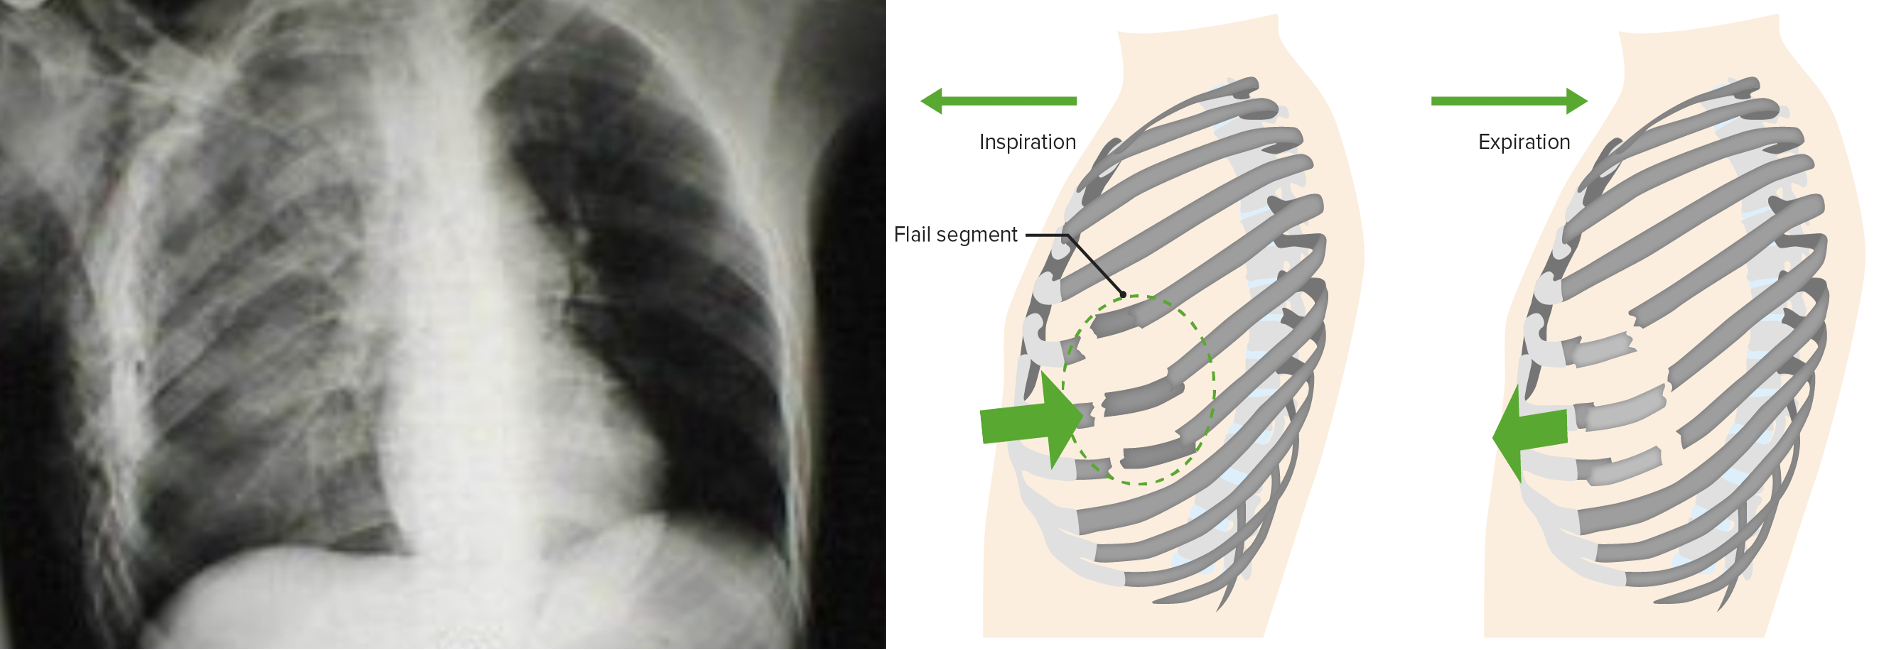

Flail chest with pulmonary contusion

• Three or more ribs fractured in at least two locations

• Paradoxical movement of “free-floating segment” may occasionally compromise ventilation.

• More importantly, an underlying pulmonary contusion may compromise oxygenation or ventilation

• Initial chest x-ray underestimates the degree of contusion

• The lesion evolve with time and fluid resuscitation